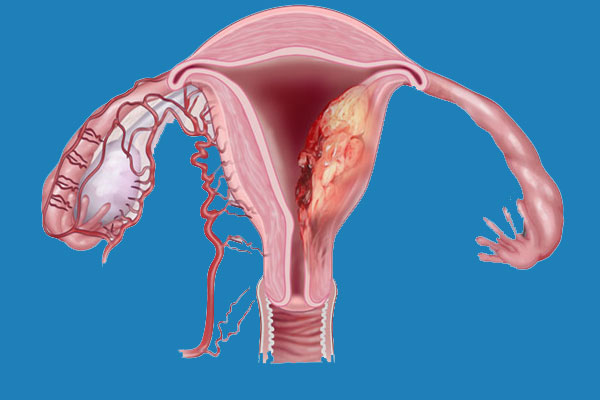

تشکیل کیستها: در برخی موارد، اندومتریوز میتواند منجر به تشکیل کیستهایی به نام "اندومتریوما" در تخمدانها شود که ممکن است دردناک باشند و حتی در صورت عدم درمان، به جراحی نیاز پیدا کند.

یکی از ویژگیهای بارز اندومتریوز ایجاد کیستهایی به نام اندومتریوما (یا "کیست شکلاتی") است که در تخمدانها یافت میشود. این کیستها از خون و بافت مشابه اندومتر تشکیل شدهاند. سونوگرافی میتواند این کیستها را به وضوح شناسایی کند. در تصاویر سونوگرافی، کیستهای اندومتریوز معمولاً به صورت تودههای گرد و یا بیضی با محتوای داخلی خاص دیده میشوند که ممکن است به رنگ تیرهتر از سایر بافتها ظاهر شوند.

شناسایی تغییرات در رحم و تخمدانها

در برخی از موارد، اندومتریوز میتواند موجب تغییرات در بافت رحم یا تخمدانها شود. سونوگرافی میتواند در تشخیص تومورهای غیرمعمول یا ضخیم شدن دیواره رحم (که ممکن است ناشی از اندومتریوز باشد) کمک کند. همچنین این روش میتواند به شناسایی و ارزیابی وضعیت تخمدانها در بیمارانی که دارای اندومتریوز هستند، کمک کند.

آندومتر با قرارگیری غیر طبیعی می تواند در طول چرخه قاعدگی رشد کرده و ریزش کند و باعث خونریزی در بین دوره ها شود. التهاب، کیست، بافت اسکار و چسبندگی ممکن است ایجاد شود که منجر به مشکلات روده، بیماری التهابی مزمن لگن یا ناباروری شود.

علائمی که در آندومتریوز مشاهده می شود به دلیل قطعات پراکنده آندومتر در حفره شکمی است. تحت تأثیر هورمون های جنسی، این قطعات تکثیر شده و خونریزی می کنند و باعث التهاب موضعی و ایجاد کیست، زخم و چسبندگی فیبری بین اندام های شکم (خارج از رحم، لوله های فالوپ، تخمدان ها، رباط های بین رحم و لگن، رکتوم می شوند). مثانه، روده ها، دیافراگم، صفاق، کلیه ها و غیره)